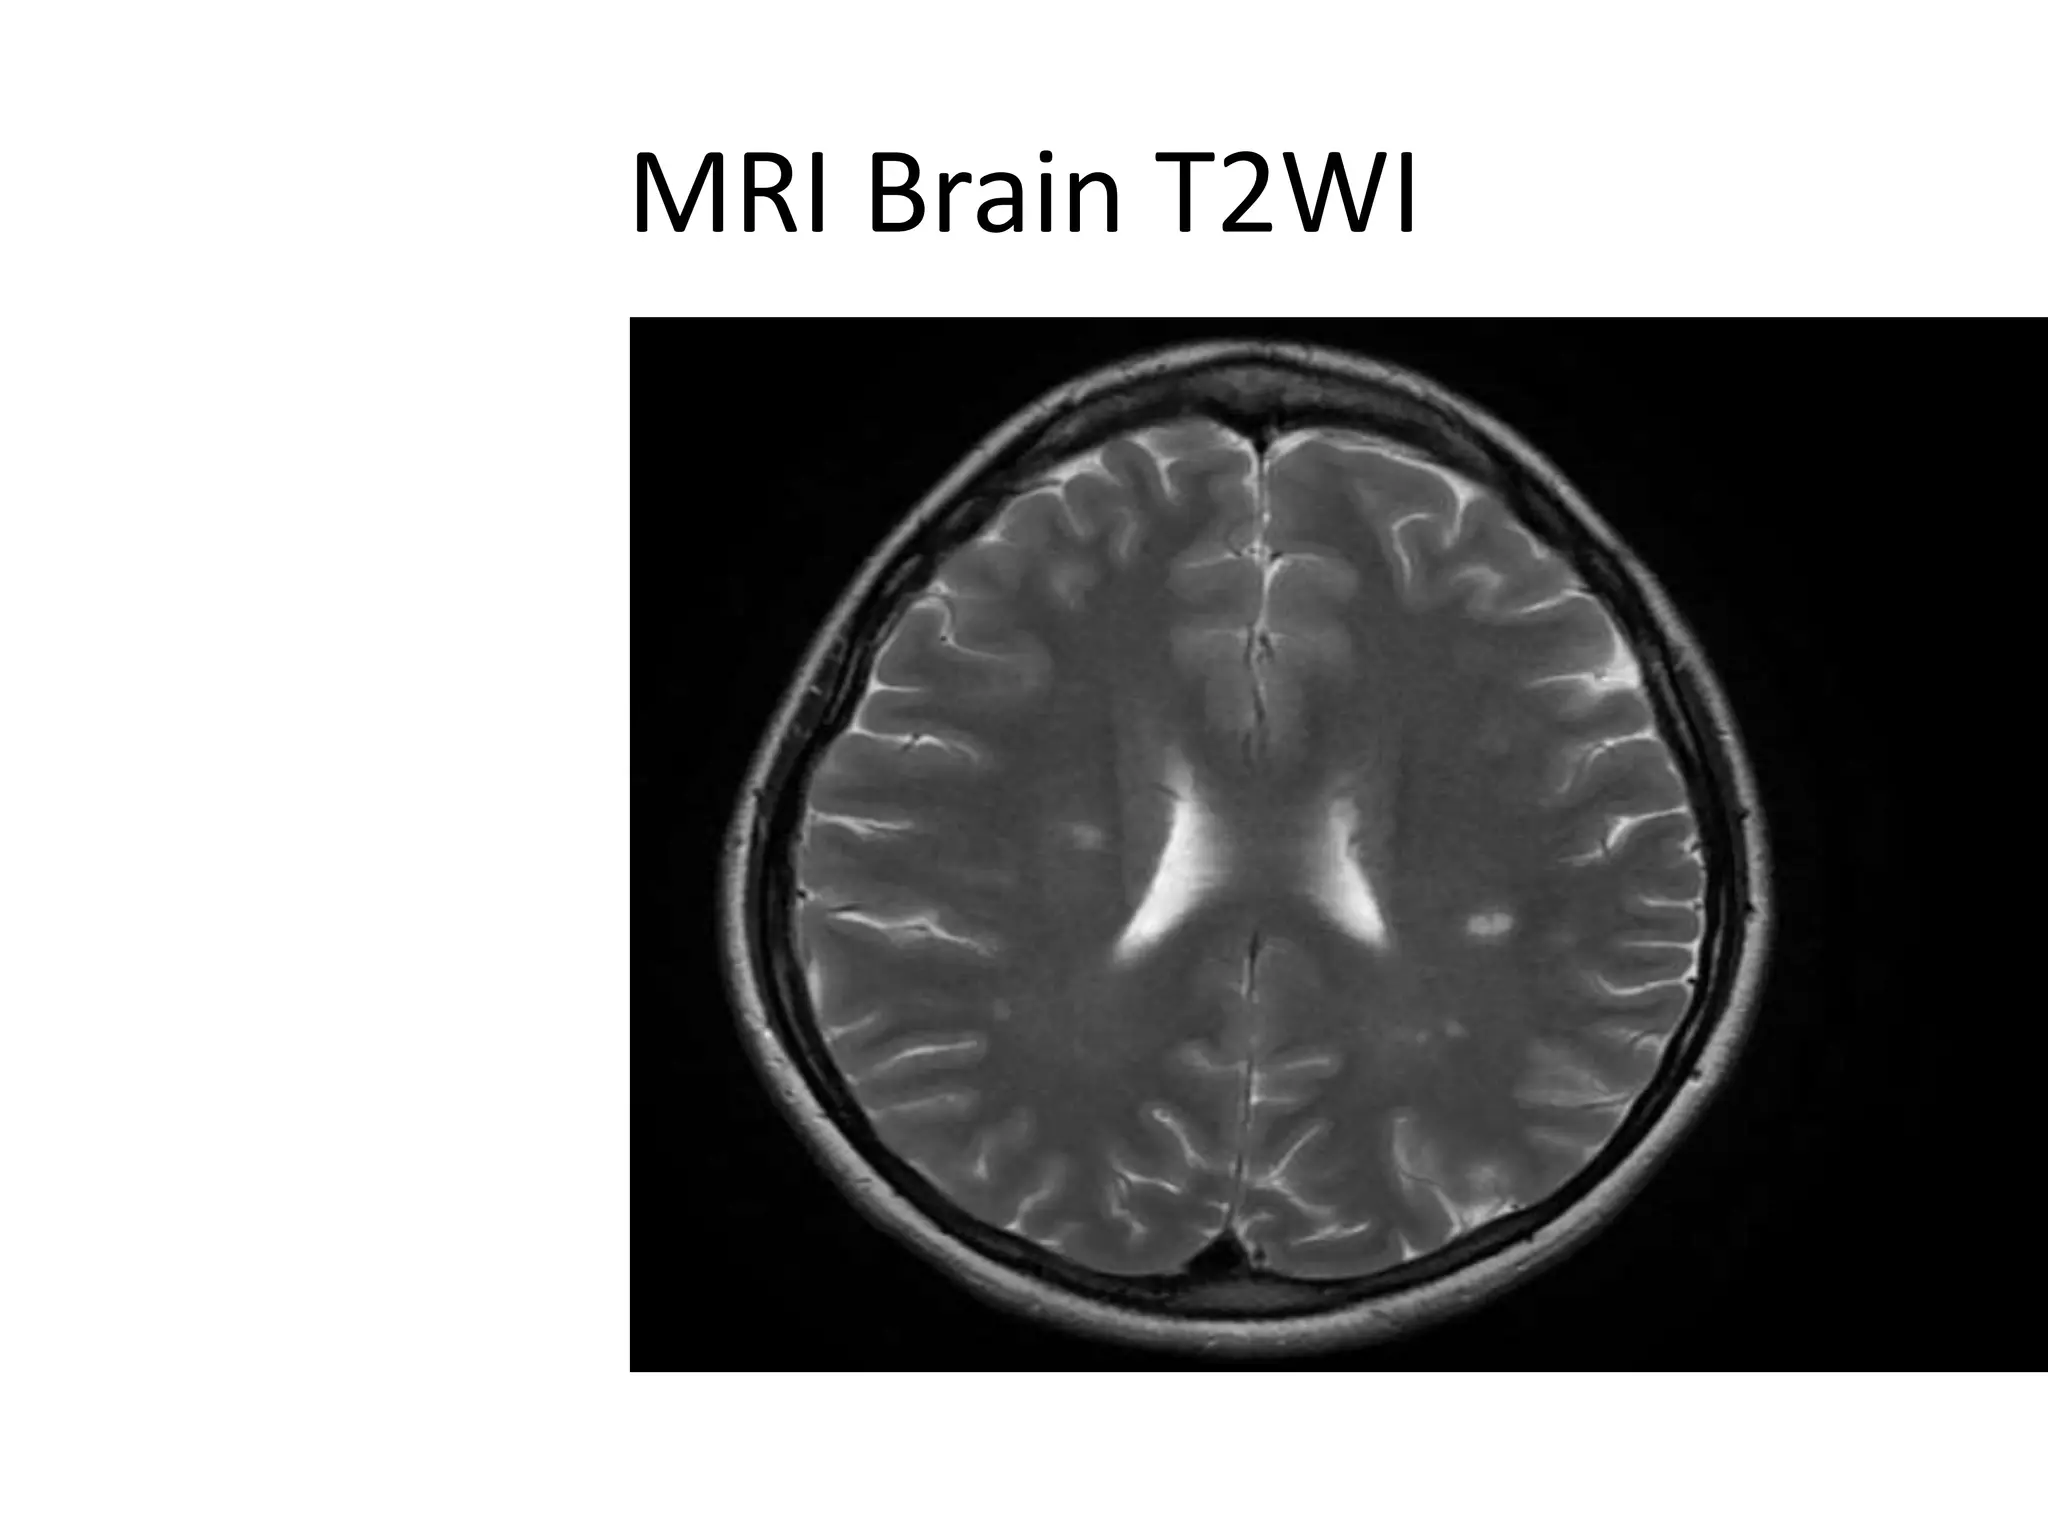

MRI Brain DIS

MRI Brain T2WI